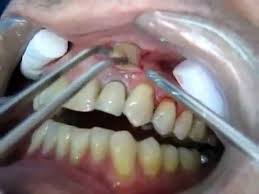

Suelen aparecer en los tejidos blandos localizados junto a un diente o una muela cuya raíz ha quedado afectada por una infección que no encuentra salida. Se trata de unas pequeñas bolsas de pus causadas por una infección de origen bacteriano. Un absceso gingival también llamado absceso periodontal que suele ser causado por una infección en el espacio entre el diente y la encía.

Un flemón dental es el nombre coloquial que recibe un absceso dental. Los abscesos o forúnculos son acumulaciones de pus inflamadas que causan dolor y se deben a una infección bacteriana.

Drenaje De Absceso Youtube